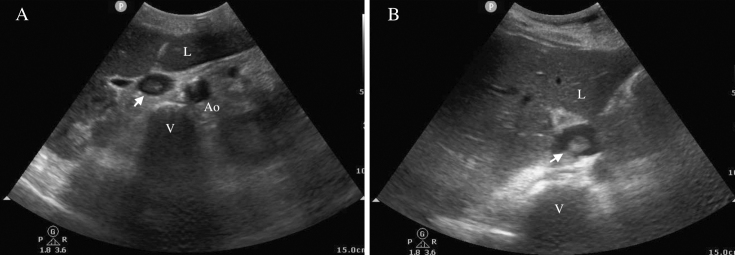

下腔静脉血栓与血管内温度管理导管有关。

Inferior Vena Cava Thrombi Related to Intravascular Temperature Management Catheters.